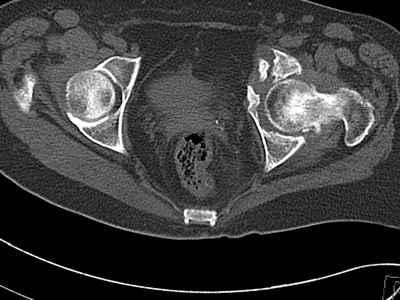

Уважаемые коллеги, возник вопрос по лечению нашей пациентки 60 лет. Около года назад множественная травма: в том числе Т-образный перелом вертлужной впадины. На сегодняшний день сращение отломков имеется на ограниченных участках, имеется дефект задней колонны вертлужной впадины. Движения неплохие, ходит с костылями, приступая на ногу. По мнению эдопротезистов при установке антипротрузионного кольца или октопуса не хватит костного материала и необходимо перед протезированием выполнить реконструкцию впадины, иначе чашка протеза неминуемо выпадет.Просьбы поделиться положительным и отрицательным опытом протезирования в подобных случаях.Возможно ли обойтись без реконструкции?Или лучше с ней?С уважением РАВ.